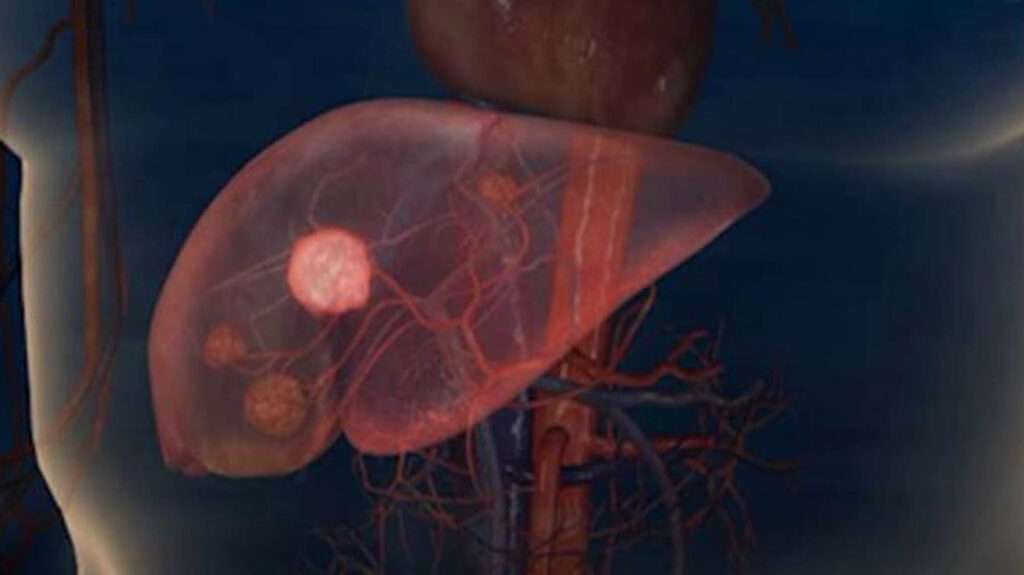

Las neoplasias benignas del hígado deben diferenciarse del carcinoma hepatocelular, el colangiocarcinoma intrahepático y las metástasis debido a que estas últimas son condiciones malignas que requieren un tratamiento y manejo clínico completamente distinto. La correcta identificación de estas lesiones es esencial, ya que las opciones terapéuticas y el pronóstico dependen de su naturaleza benigna o maligna.

Entre las neoplasias benignas más comunes del hígado, se encuentra el hemangioma cavernoso, una lesión vasculosa que generalmente se descubre incidentalmente en estudios de imagen como ultrasonografía o tomografía computarizada (TC). Aunque el hemangioma cavernoso es una lesión benigna, puede aumentar de tamaño en mujeres que toman terapia hormonal, lo que podría dar lugar a la preocupación de que se trate de una lesión maligna. La diferenciación de esta neoplasia de otras lesiones hepáticas que ocupan espacio es fundamental para evitar diagnósticos erróneos. Para ello, se utilizan técnicas de imagen avanzadas como la resonancia magnética (RM), TC o ultrasonografía con contraste, las cuales permiten obtener una imagen detallada de la lesión, evaluando su tamaño, bordes y patrón de vascularización, características que permiten una correcta clasificación.

Otro tipo de neoplasia benigna del hígado es la hiperplasia nodular focal, que puede presentarse a cualquier edad y en ambos sexos, sin embargo, en las mujeres no se asocia con el uso de anticonceptivos orales, lo que la distingue de otras lesiones hepáticas hormonodependientes. Esta condición se caracteriza por la formación de una masa hipervascular, generalmente con una cicatriz central hipodensa que adopta una forma «estelada», visible en estudios con contraste. Su aparición es típicamente asintomática, lo que contribuye a su diagnóstico incidental. Además, la hiperplasia nodular focal puede encontrarse en pacientes con cirrosis hepática o en aquellos que han estado expuestos a fármacos inmunosupresores como la azatioprina, así como en personas con síndrome antifosfolípido. La presencia de hemangiomas hepáticos en pacientes con hiperplasia nodular focal sugiere una posible relación entre ambas condiciones, lo que hace necesario tener en cuenta los antecedentes clínicos del paciente al momento de realizar el diagnóstico diferencial.

El adenoma hepatocelular es otro tipo de neoplasia benigna del hígado, que suele afectar a mujeres jóvenes en la tercera y cuarta décadas de la vida. Esta neoplasia está frecuentemente asociada al uso de anticonceptivos orales, los cuales pueden inducir un crecimiento anormal de los hepatocitos. Aunque la mayoría de los adenomas hepatocelulares son benignos, algunos pueden sufrir necrosis o hemorragia, lo que puede provocar dolor abdominal agudo y complicaciones adicionales. En este contexto, resulta esencial realizar un seguimiento cercano, ya que algunos adenomas hepatocelulares tienen variantes patogénicas asociadas a un mayor riesgo de transformación maligna. Por lo tanto, la diferenciación de este tumor de neoplasias malignas como el carcinoma hepatocelular es crucial, y se debe hacer mediante un análisis detallado de las características radiológicas, histológicas y clínicas del tumor.

En cuanto a las neoplasias quísticas mucinosas del hígado, anteriormente denominadas cistadenoma y cistadenocarcinoma, también deben diferenciarse de otras lesiones quísticas benignas del hígado, como los quistes simples, los equinocócicos, los complejos de Von Meyenburg (hamartomas) y la enfermedad hepática poliquística. La diferenciación entre estos tipos de quistes es esencial, ya que algunos pueden tener un comportamiento maligno, especialmente cuando se encuentran lesiones complejas con características sospechosas de transformación neoplásica. Para ello, se utilizan métodos de imagen avanzados, como la TC y la RM, que permiten caracterizar las paredes de los quistes, la presencia de septos o masas dentro de ellos, así como la vascularización y la distribución de los fluidos internos.